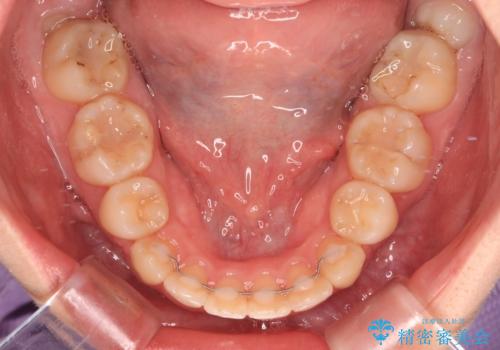

- 前歯のデコボコと突出感を気にして来院された患者様です。

上下左右第一小臼歯4本を抜歯して、積極的に口元を引っ込めるよう、ワイヤー装置にて矯正治療を行うこととしました。

口の閉じにくさが改善され、横顔のシルエットも大幅に改善されました。